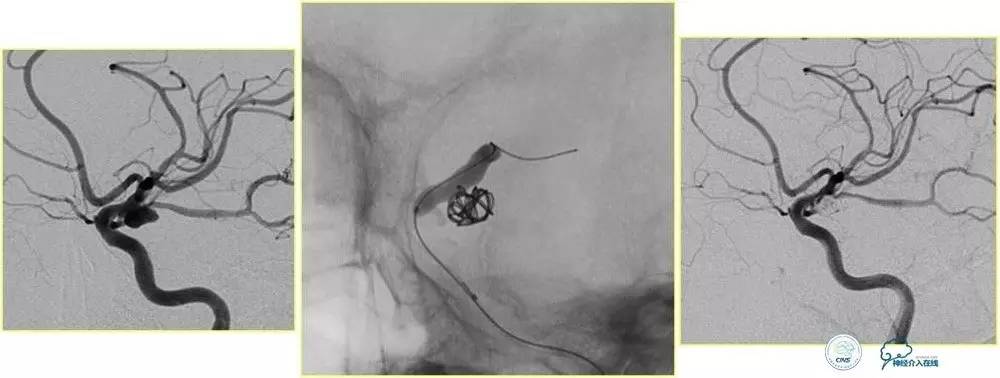

小脑幕缘区DAVF,只有颈外动脉参与供血,供血支细小。

选择抑制血管栓塞,胶无法弥散进入瘘口,选择另一支血管,近端防止Hyperform球囊。

最终胶弥散结果,瘘口完全消失。

小脑幕缘区DAVF,颈外动脉和颈内动脉的供血支均非常细小。

Marathon微导管进入分支后,在主干血管内放置Hyperform球囊。

最终的栓塞结果。